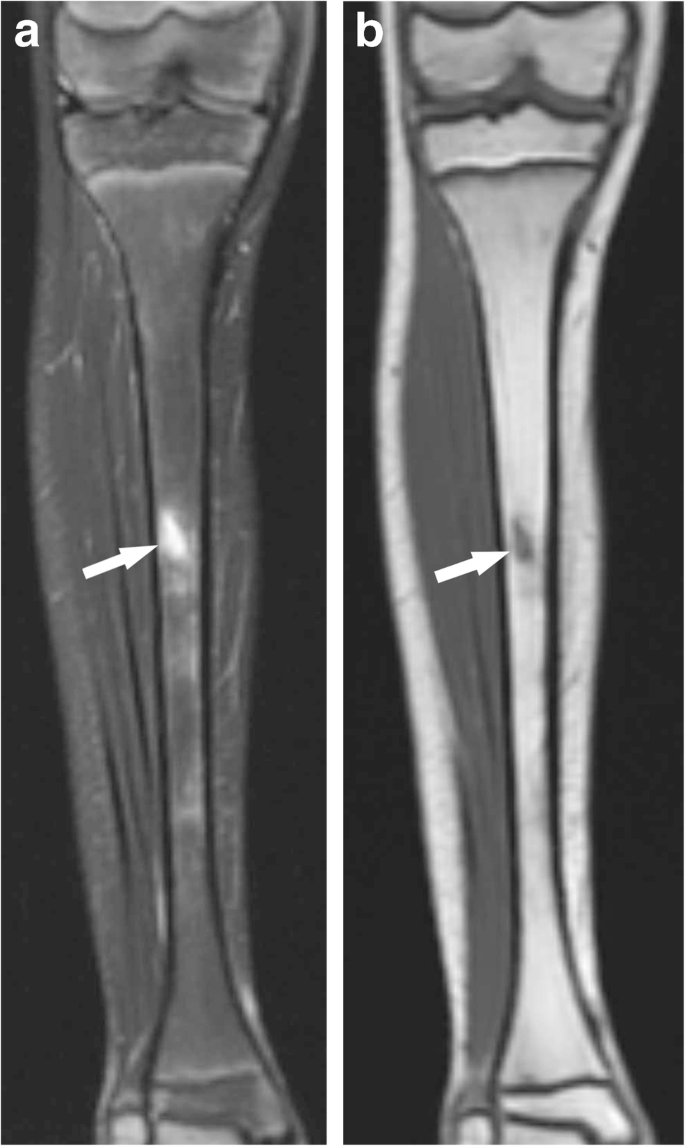

Endochondral ossification

•hyaline cartilage → bone

•femur, humerus, tibia, vertebrae, pelvis, and base of skull